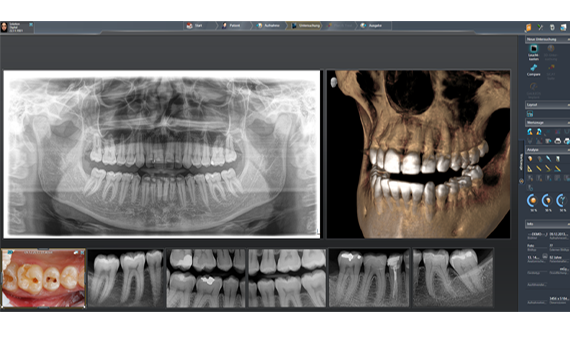

在灯箱中,您可以同时比较2D和3D图像、内窥镜画面和面阵扫描数据。

Sidexis 4数字灯箱灵活性强,可在软件界面上无缝显示所有图像类型。所有2D、3D和口内图像都可以同时处理和查看,以确保所有图像数据都可用于诊断过程。例如,可以对口内图像和3D扫描进行快速确切的交叉比较,从而极大简化诊断和治疗计划过程。因此,从患者咨询到治疗计划和模拟,这款直观的软件为您的诊断提供了理想的条件。

有了时间轴,患者的全部病史一目了然。这可让您在诊断选项中添加直观的时间维度。

Sidexis 4直观的用户界面和显示器可以显示各种图像,例如口内图像、2D全景图像和3D图像。与其他软件不同,它可以提高您的诊疗效率和诊断准确性。登士柏西诺德的解决方案可让您针对多种不同的情况给出治疗计划,并为个别患者制定治疗方案。